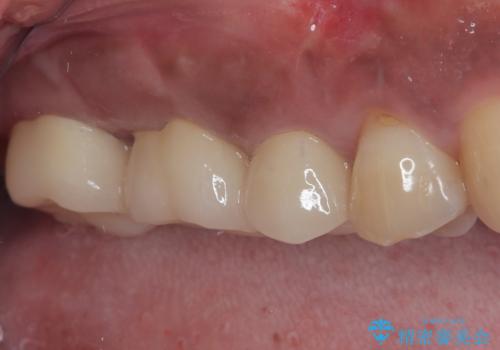

不快感の強い奥歯 オールセラミッククラウンでのむし歯治療

- とにかく奥歯に不快感を感じるとのことで来院された患者様です。

神経近くにまで及んでいる大きなむし歯や、歯肉の中深く、骨の近くにまでむし歯が進行している歯など、問題の多い状態でした。

神経を温存するための処置や、歯肉深くにまで及んだむし歯を改善するための歯周外科処置などを行っていき、オールセラミッククラウンにて補綴治療を行うこととしました。

術前の診断では神経が温存できるか否か、際どい状況でしたが、治療開始前の海外への帰省の際に自発痛(何もしなくてもズキズキ痛む)の症状が出てしまい、根管治療が必要となってしまいました。